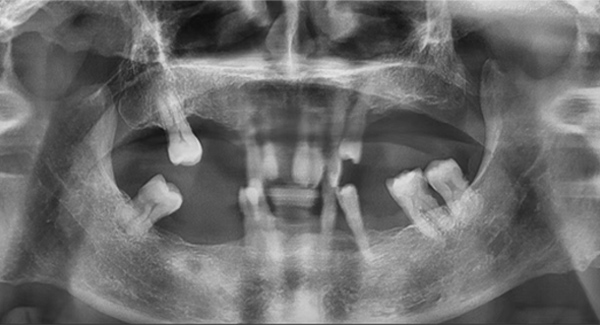

全口病例:咬合重建,磨刀不誤砍柴功

另一個全口種植案例,除了缺牙、骨量等常見問題外,他的咬合還是內(nèi)傾的深覆合,這是最大的治療難點。也就是說,患者的咬合不正常,如果按常規(guī)的思路種植后直接戴臨時牙冠,當(dāng)他半年后戴上最終牙冠時,整個咬合可能不會理想,到那個階段再去調(diào)整咬合,效果可能不太好,人也比較受罪。

我決定做難但正確的事情。種植手術(shù)完成后,我讓患者戴上了樹脂義齒重建咬合,讓他通過日常的咀嚼,在原本平整的下牙義齒上慢慢形成新的尖窩對應(yīng)關(guān)系。前后花了半年時間,才達(dá)到穩(wěn)定且可重復(fù)的咬合狀態(tài)。這時候,再制作第二幅臨時義齒,也就是有解剖牙尖和尖窩交錯關(guān)系的臨時牙,讓患者再次適應(yīng)咬合3個月。最后,我把患者適應(yīng)并且滿意的咬合關(guān)系轉(zhuǎn)移到他的最終牙冠上,完成了修復(fù)治療。

這位患者不到60歲,但由于后牙全部缺失多年,殘留的前牙已松動且上下無法接觸,他基本沒辦法正常咀嚼,人非常消瘦。完成治療后我跟蹤了這個病例一年,從前后對比照片可以看出,能正常吃東西后他的臉上漸漸也有肉了。